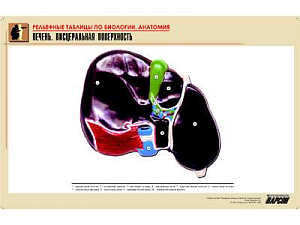

Объёмные модели и муляжи. Модель клетки, скелеты позвоночных, муляжи внутренних органов человека, барельефные таблицы по разделам зоологии и ботаники. На ЕГЭ и ОГЭ задания по анатомии и систематике — одни из самых частых. Объёмная модель отрабатывает пространственное представление так, как плоская картинка не может.